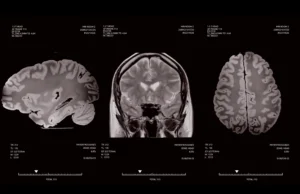

La intersecția dintre tehnologie și îngrijire medicală, ICCO EMS oferă echipamente și servicii inovatoare pentru neurochirurgie, radioterapie, radioprotecție, iradiere sânge și recuperare medicală.

Furnizăm echipamente medicale avansate, selectate pentru performanță, siguranță și fiabilitate în domenii critice precum oncologia, radioterapia și neurochirurgia.